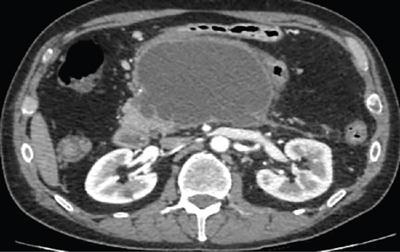

Shrinivas B. Desai, Ritu K. Kashikar, Shreya Shukla Radiological signs are classical and distinctive abnormalities characteristic of a disease. These can be seen on any imaging modality. Resemblance to commonly seen objects and patterns form the basis of radiological signs. The aim is to help the reader associate, understand and memorize these pathologies with the aid of signs. Various signs pertinent to hepatobiliary system are described in the chapter. Described on MRI when liver lesion shows a peripheral rim of high T2 signal intensity with the centre of the lesion appearing isointense to the background of noncirrhotic liver on T2WI mimicking an atoll. It is considered a characteristic sign of an inflammatory hepatic adenoma (image) but is only seen in about one-third of cases Extrinsic smooth impression over medial aspect of duodenum along its posteroinferior aspect, seen in pancreatic head pathologies like carcinoma. This sign is seen in pancreatic adenocarcinoma Presence of a persistently hyperattenuating dot within a lesion on arterial and portal venous CT. This corresponds with peripheral nodular enhancement seen on dynamic MR. Presence of bright dot suggests that the lesion is a hemangioma and helps in ruling out metastasis Ultrasound appearance of multiple cystic spaces or lesions that has been used to describe the appearance of an intraductal papillary mucinous neoplasm of the pancreas. Seen on contrast CT in portal hypertension. The appearance is based on resemblance to Medusa from Greek mythology. Dilated engorged paraumbilical veins radiating across umbilicus to join systemic veins is seen. This sign is seen in Caroli’s disease on contrast CT. Enhancing dots within dilated intrahepatic bile ducts represent portal radicles. Caroli’s disease Irregularly dilated pancreatic duct with multiple strictures and intervening dilatation with associated dilated side ductules resemble multiple lakes supplied by a single territory. Best seen in MRCP images. Chronic pancreatitis It is a finding on MRI and CT and is best seen on MRI T2-weighted and postcontrast T1-weighted sequences. Small necrotic/purulent areas in the pyogenic abscess ‘cluster’ together and then coalesce into a larger necrotic/purulent areas, eventually becoming a larger septated abscess cavity. At the periphery of these clusters: Associated with pyogenic hepatic abscesses and can help differentiate pyogenic abscesses from other types of liver lesions Abrupt termination of gas within the proximal colon at the level of radiological splenic flexure. The inflammatory exudates in pancreatitis extend to the phrenicocolic ligament giving rise to this sign Seen on grey scale ultrasound as a reverberation artifact when small calcific or highly reflective objects are imaged. The colour comet-tail artifact is an ultrasonographic sign seen in a number of situations when colour Doppler scanning is performed. This sign occurs in cases of traumatic right-sided diaphragmatic rupture with resultant partial herniation of liver through the defect. Separation of the herniated liver from its intra-abdominal component is via a small constriction at the level of diaphragm resembling a cottage loaf. Cottage loaf is a particular shape of bread in which larger and smaller roughly spherical balls are squashed together. Traumatic right-sided diaphragmatic rupture with resultant partial herniation of liver Bile eccentrically outlines luminal stone, creating a low attenuation crescent. Best seen on MRCP images. Choledocholithiasis Dilatation of both pancreatic duct and CBD is referred to as the double duct sign. Positive double duct sign suggests the diagnosis of carcinoma of the head of the pancreas and ampullary tumours and is hence considered ominous. Occasionally the sign may be seen in impacted gallstone in the distal duct. This feature is seen in patients with liver abscess on contrast-enhanced CT. A double, inner hyperattenuating and outer hypoattenuating rim is seen surrounding the hypodense abscess. The inner hyperattenuating rim corresponds to the enhancing abscess membrane, while the outer rim corresponds to the edema of the surrounding liver which appears hypodense and may show delayed enhancement. Liver abscess A positive duct penetrating sign is when a mass is penetrated by an unobstructed pancreatic duct; this makes focal pancreatitis the most likely cause rather than pancreatic carcinoma. This sign is best appreciated on MRCP (or ERCP). A radiographic sign that can be useful in differentiating between focal pancreatitis (inflammatory pancreatic mass) from pancreatic carcinoma. The duct-penetrating sign on MRCP is more helpful in differentiating between these two entities than a delayed enhancement pattern on CT or MRI It occurs when there is both limy bile and a gallstone in the common bile duct. The linear vertical radiopaque bile forms the line of the exclamation mark (i.e. !), whilst a more distal calculus forms the ‘dot’ at the end of the exclamation mark. Pathognomonic imaging sign of the rare diagnosis of limy bile on plain abdominal radiography Nonenhancing ruptured lesion with peripheral rim enhancement showing discontinuity from the rest of the liver and protruding from the liver surface is called the enucleation sign. Ruptured HCC Enlargement of the pericholecystic space. One of the signs of liver cirrhosis Can be seen on technetium 99m sulphur colloid scans of the liver and spleen, as well as CT studies. It occurs as a focal area of increased radiopharmaceutical uptake in the medial segment of the left hepatic lobe (segment IV) occurring as a result of SVC obstruction and portosystemic venous shunting between the superior vena cava and the left portal vein via the internal thoracic and paraumbilical veins. The equivalent of this sign may also be seen on contrast-enhanced CT scans as a hypervascular region. Budd–Chiari syndrome causes the hot spot sign in the caudate lobe